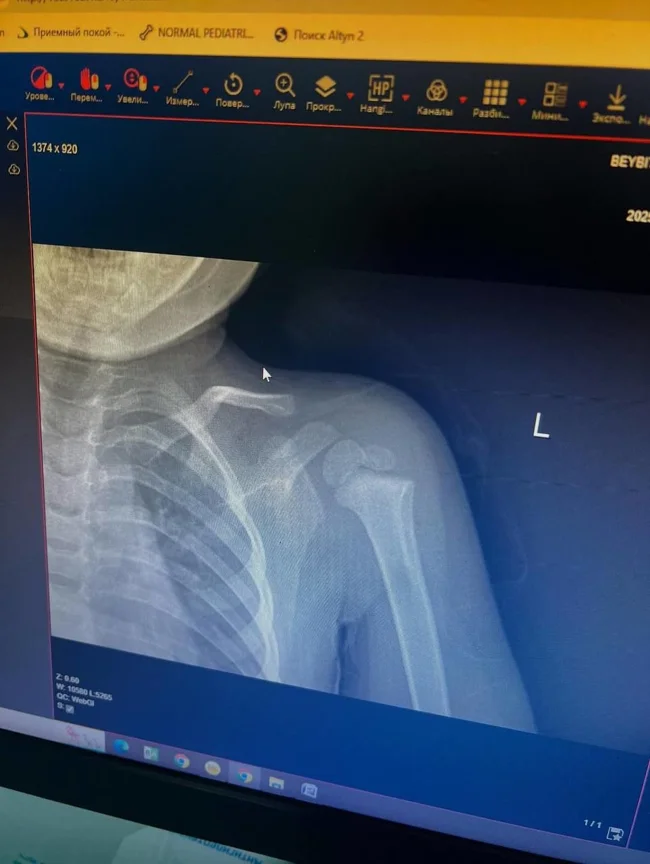

В Алмати 13-річний підліток схопив дворічну дитину та з силою кинув її на асфальт. У малюка діагностовано перелом.